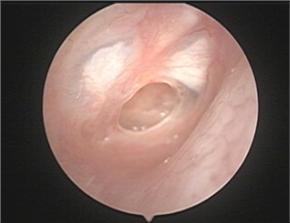

2、耳内窥镜检查。内窥镜是一种光学仪器,由体外经过耳道送入,对耳道鼓膜疾病进行检查,可以直接观察到耳道、鼓膜凹陷、穿孔等,确定其部位、范围,并可进行照相、活检或刷片,大大的提高了传导性耳聋的诊断准确率,并且可以检查助听器喇叭的腐蚀状况。

图为可将耳部病灶放大500倍成像的耳内窥镜